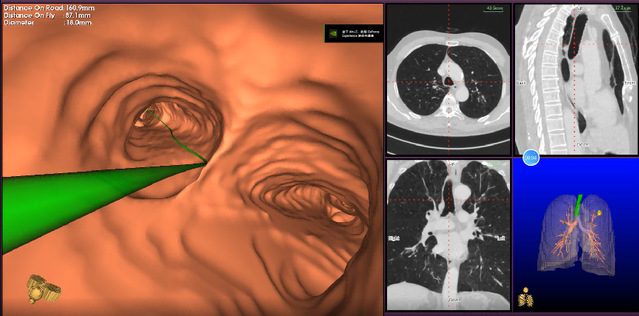

作为介入呼吸病学的**进展,电磁导航支气管镜技术是现代电磁导航技术、虚拟支气管镜和三维CT成像技术相结合的新一代支气管镜检查系统。该系统如同肺部的GPS导航系统,能够建立一条直达肺内病灶的精准诊疗通道,对肺部病变尤其是肺小结节病灶的诊断更准确,与传统诊断方法比较有显著的优势。探花直播 呼吸与危重症医学科副主任董凌云提前将李先生的高分辨率CT图像导入磁导航系统,构建确定了“GPS导航”路径。在麻醉医生的配合下,呼吸与危重症医学科副主任张剑锋利用电磁导航支气管镜诊疗技术,在纵横交错的“支气管交通网”中,按照系统提前规划的“GPS导航”路径,可视化操作支气管镜,精准到达左肺上叶后段结节处“目的地”,成功获取了左肺上叶后段结节的病理活检组织,并给予肺泡灌洗送NGS检测,顺利完成吴江区域内首例“电磁导航支气管镜检查”,开启了吴江地区肺部外周病灶精准诊疗模式。

近年来,随着计算机断层扫描肺部筛查的普及,筛查期间发现了很多的外周型肺结节,这些外周型肺结节的性质单从影像学上无法分辨,明确诊断需依靠病理检查。但经气管镜穿刺或活检很多时候无法到达外周型肺结节的位置,可能需要进行并发咯血、气胸、血胸等风险较高的CT引导下经皮肺穿刺才能取到病理,且该项检查患者辐射暴露的风险亦增加。而磁导航支气管镜检查则突破了传统支气管镜检查的应用瓶颈,该项检查是一种将磁导航系统、支气管镜检查以及CT三维重建技术相结合的新技术:在患者CT影像的基础上,通过建立肺部“GPS导航”地图,利用体外磁场定位板来进行实时引导定位电磁导航支气管镜操作,使得定位导线和鞘管快速精准地到达肺部的每一个角落,可以精准定位肺外周靶病灶、开展活检及治疗。